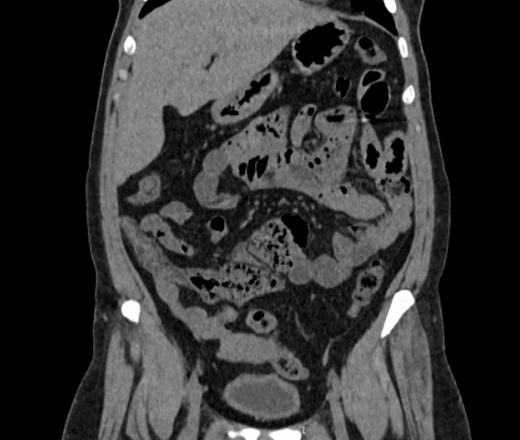

Здравствуйте, женщина 40лет, жалобы на увеличение живота, началось с 2023 года, жалобы на запоры временами и на водянистый стул, подскажите что здесь в области баугиниевой заслонки? инвагинация слепой кишки в подвздошную? что рекомендовать?

В классической рентгенологии такое смещение слепой кишки называли - мобильная слепая кишка.

Описал бы как "кт-признаки болезни Крона (терминальный илеит)", порекомендовал бы колоноскопию с биопсией